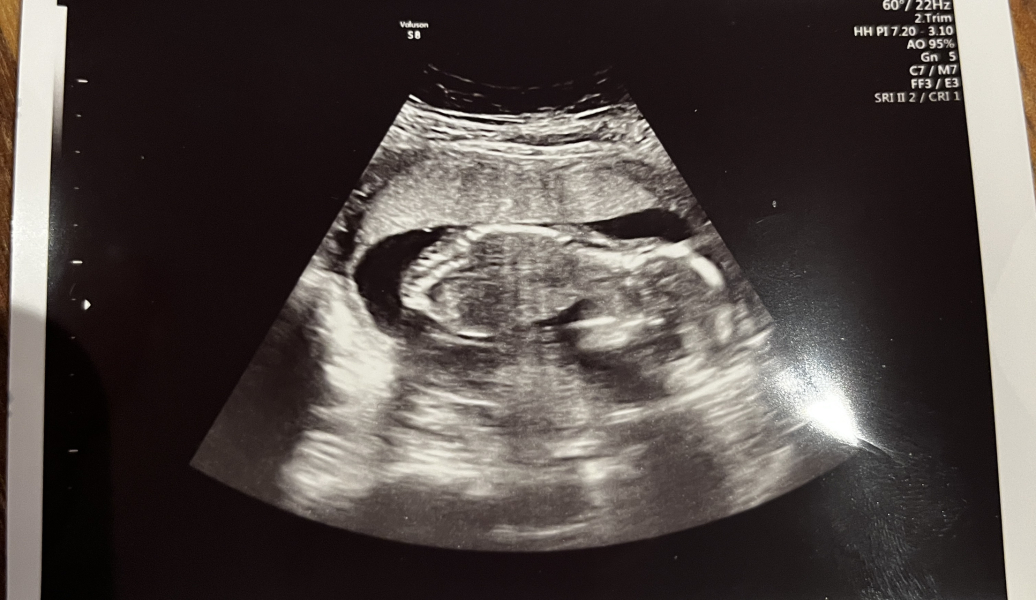

@bringmearainbow amazing news!!! I would say boy based on your scan pic 😍. I love being a boy mama, so glad everything is going well and you're also able to get the HB to listen too, it really is amazing, I totally miss being pregnant!

@FfoxRedN ahhhh hey lovely lady ❤️ I def think the 12 week scan looked more boy nub but I'm def no expert on it 😂 also at the scan on Friday he straight away asked if we want to know and when we said no he immediately moved the scan to a different spot so the image changed and I think they only do that very quickly when there's an obvious protruding object to see😂 I'm really 50/50 I'd love to have a girl to experience having one and all the cute girl stuff but at the same time I have tonnes and tonnes of boy stuff and I really think it would be lovely for DS to have a brother and I have loved being a boy mum 🙊

@MrsJGrealish hahaha yes sorry talking about dogs now 🤣 lol some pictures I'm like is there even one there 😂 tbf I thought this was one of the clearest scan pics I've had I looked back on DS and there was no nub in sight it was a terrible picture

@bringmearainbow amazing!! That scan pic is so clear!! You know my scan pic was super clear too and I could already see on the scan as the nub was sooo obvious. And it was super obvious on my photo. A during my scan at 13 weeks I thought that’s a girl nub. It’s a girl. An I was right. I just knew it.

If what I can see is yours is a nub. Which I think it is… that a girl. I’m certain of it 💗 time shall tell. How exciting!!